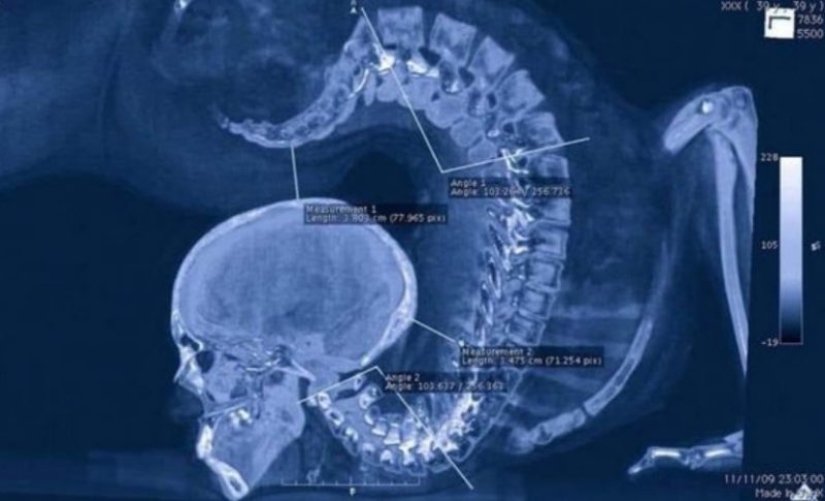

X-ray de gimnastas que hace ejercicios de piso.